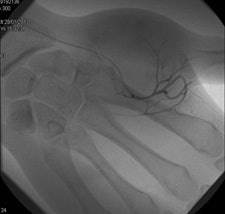

In the third year of my residency in 1982, I began to be attracted by the new way to perform interventions through percutaneous and endovascular approaches, and for a few months I went to the MD Anderson Center in Houston, Texas, U.S. There I took an important decision, which was that I would like to be completely involved in interventional radiology (IR), and with the great support of the CUN, this is what I have done for the rest of my professional life.